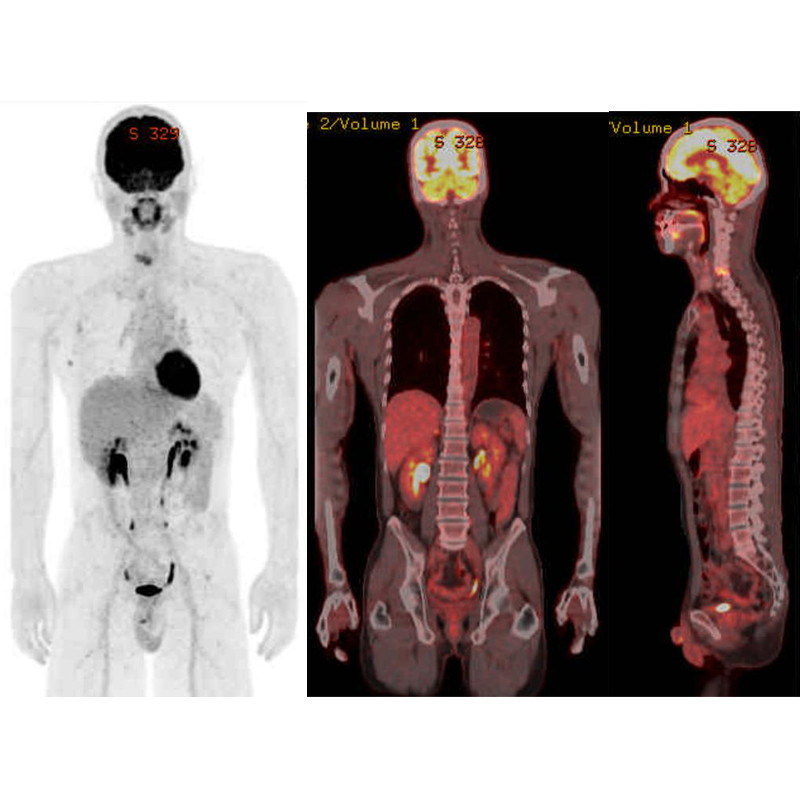

【商品コード】161-3085-003 佐久医療センター PET/CTがん検診

近年、がんの〈早期発見・早期治療〉への認識が高まり、全身を一度に検査できるPET/CT検査が注目されています。「検査って大変そう」「検査がちょっとおっくう」「一度受けたからもういい」などの理由でがん検診や検査を受けられずにいる方はいませんか? PET/CT検査は着衣のままで行いますし、痛みを伴う検査でもありません。